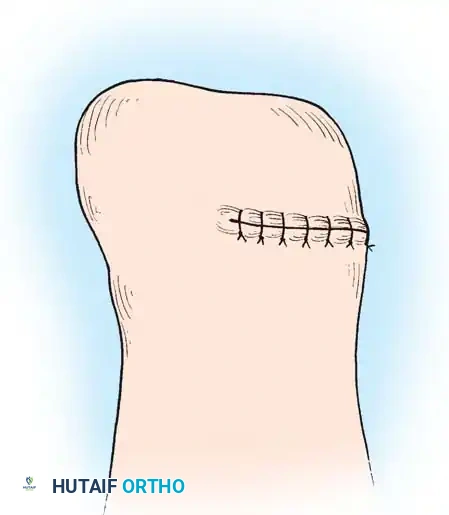

Step 7: Closure

- Approximate the skin edge of the heel flap to the anterior flap using interrupted nonabsorbable sutures. Ensure there is absolutely zero tension on the closure.

- Crucial Step: Large, protruding tags of skin ("dog ears") will form at the medial and lateral ends of the suture line. Never excise these. They carry the primary blood supply to the heel flap and will naturally remodel and shrink under postoperative bandaging.